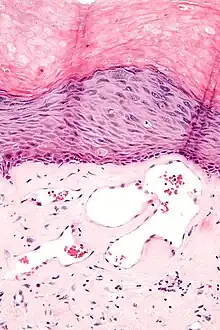

Angiokeratomas characteristically have large dilated blood vessels in the superficial dermis and hyperkeratosis (overlying the dilated vessels).

Scrotal angiokeratoma; visible large dilated blood vessels and hyperkeratosis